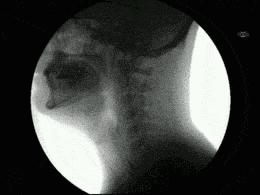

我坐在凳子上,医生两手在我脖子摸了一会儿,就说需要加B超检查。

乖乖地做了B超,我再次来到诊室,医生拿着B超单说:“确定是 甲状腺结节, 至于是良性恶性,建议进一步检查……”

目前可通过甲状腺彩超、结节穿刺细胞血检查以及基因分子检测判断结节良恶性,根据检查结果,给予相应的治疗。